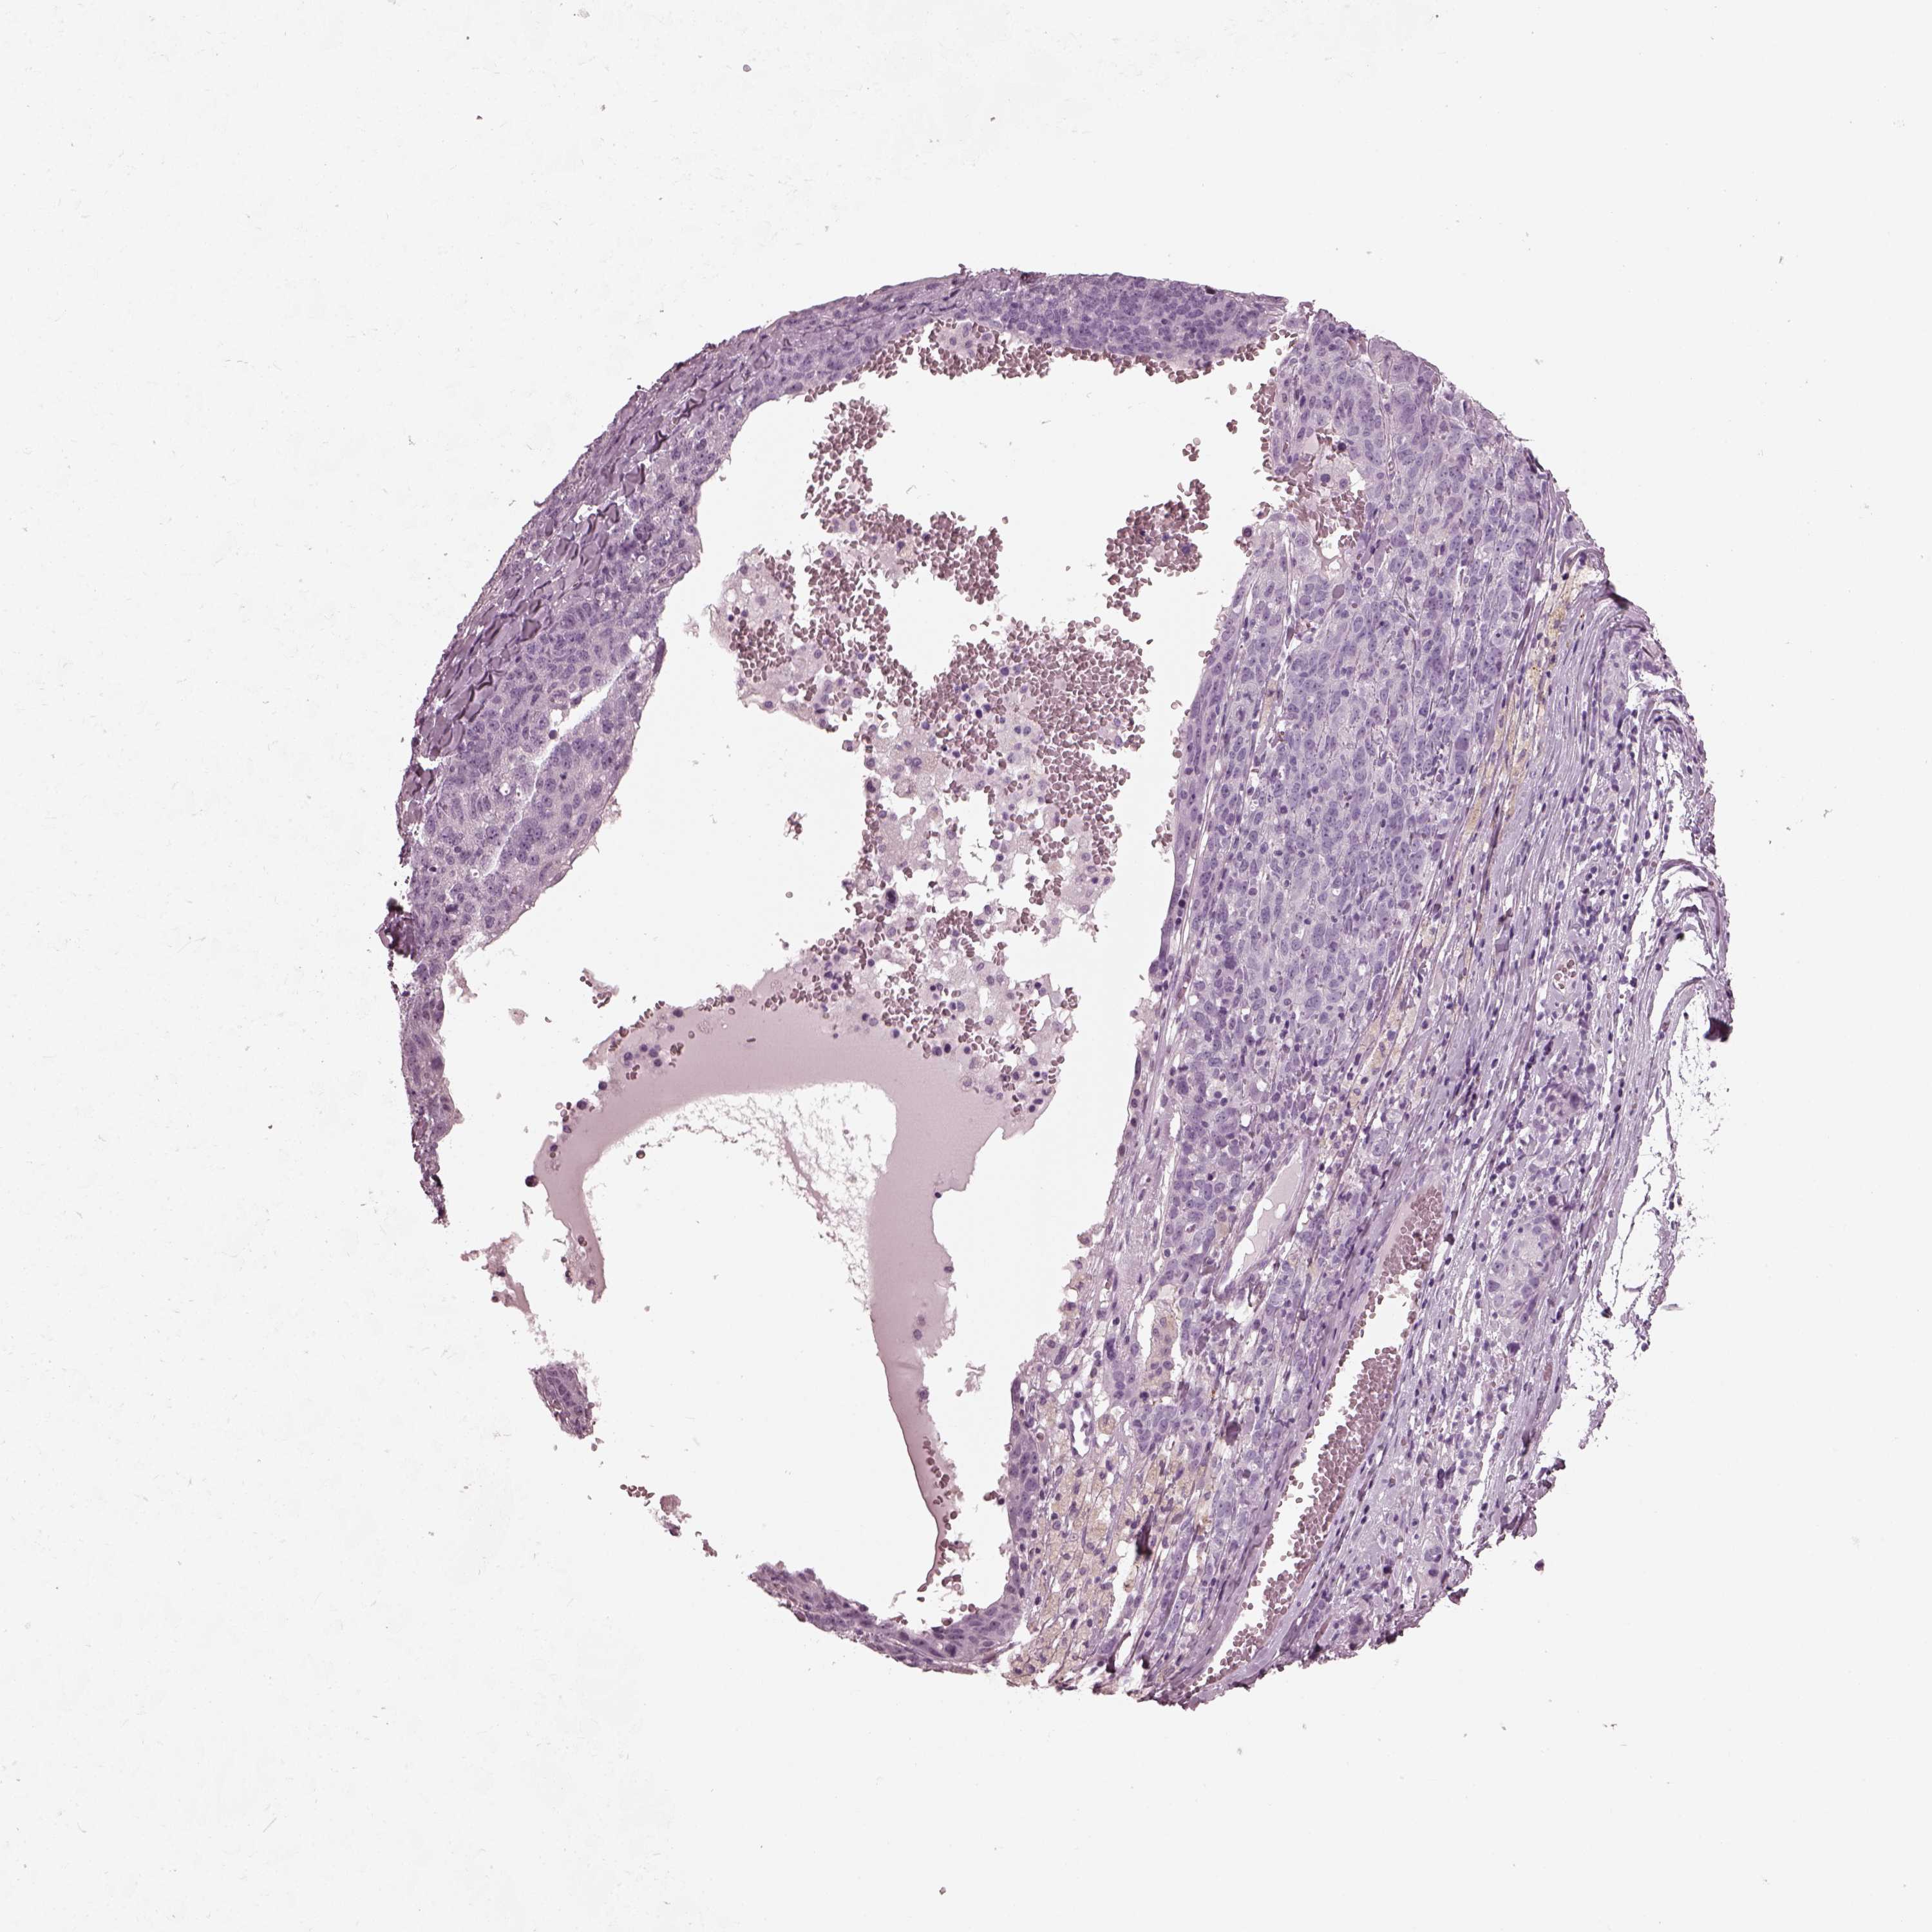

OVARIAN CANCER - Protein expressioni

A mouse-over function shows sample information and annotation data. Click on an image to view it in a full screen mode. Samples can be filtered based on level of antibody staining by selecting one or several of the following categories: high, medium, low and not detected. The assay and annotation is described here.

Note that samples used for immunohistochemistry by the Human Protein Atlas do not correspond to samples in the TCGA dataset.

Antibody stainingi

Antibody staining in the annotated cell types in the current human tissue is reported as not detected, low, medium, or high, based on conventional immunohistochemistry profiling in selected tissues. This score is based on the combination of the staining intensity and fraction of stained cells.

Each image is clickable and will lead to virtual microscopy that enables deeper exploration of all samples and also displays staining intensity scores, fraction scores and subcellular localization as well as patient and tissue information for each sample.

Antibody HPA015783

Antibody CAB022363

Cystadenocarcinoma, serous, NOS